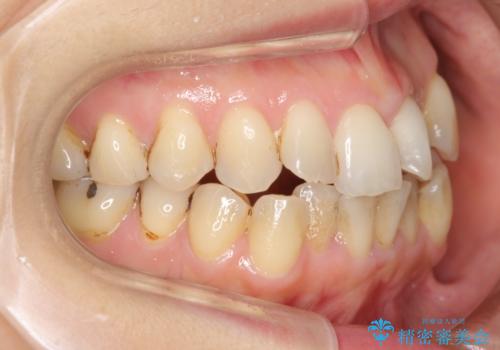

前歯は開咬傾向であり、小臼歯から大臼歯にかけてもオーバージェットは非常に小さく咬耗していました。

途中再評価を行い、矯正用のミニスクリューを用いて奥歯を遠心移動し、前歯の出っ歯傾向を改善しました。

左上12の段差についてはここまで直すのにもかなり時間がかかりました。インビザライン単独では限界があると説明し、ワイヤーの部分矯正もご提案しましたが、患者様のご希望によりインビザラインでできるところまで頑張るということで4回ほどリファインメントを行いました。